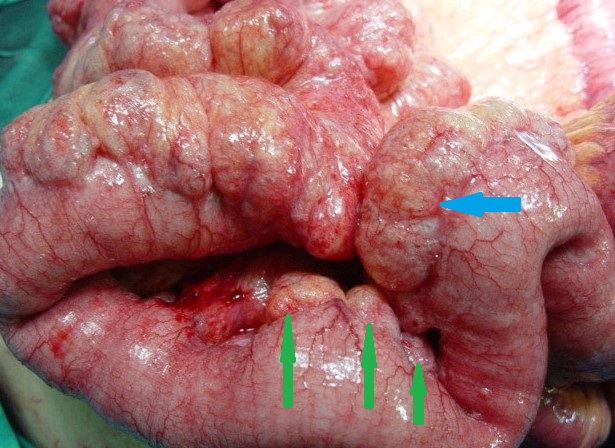

The two metastatic foci causing stenosis and bowel obstruction are clearly visible (Courtesy Dr. V. Penopoulos)